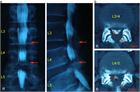

1. 頚髄症と腰部脊柱管狭窄症合併例では、頚椎手術を優先するが、腰部脊柱管狭窄症が主訴となっている場合には頚椎が伸展しないように術中体位に十分注意する。

1. 脊柱変形、骨破壊の強い例では、インスツルメンテーションを併用した後方固定を除圧術に併用する。